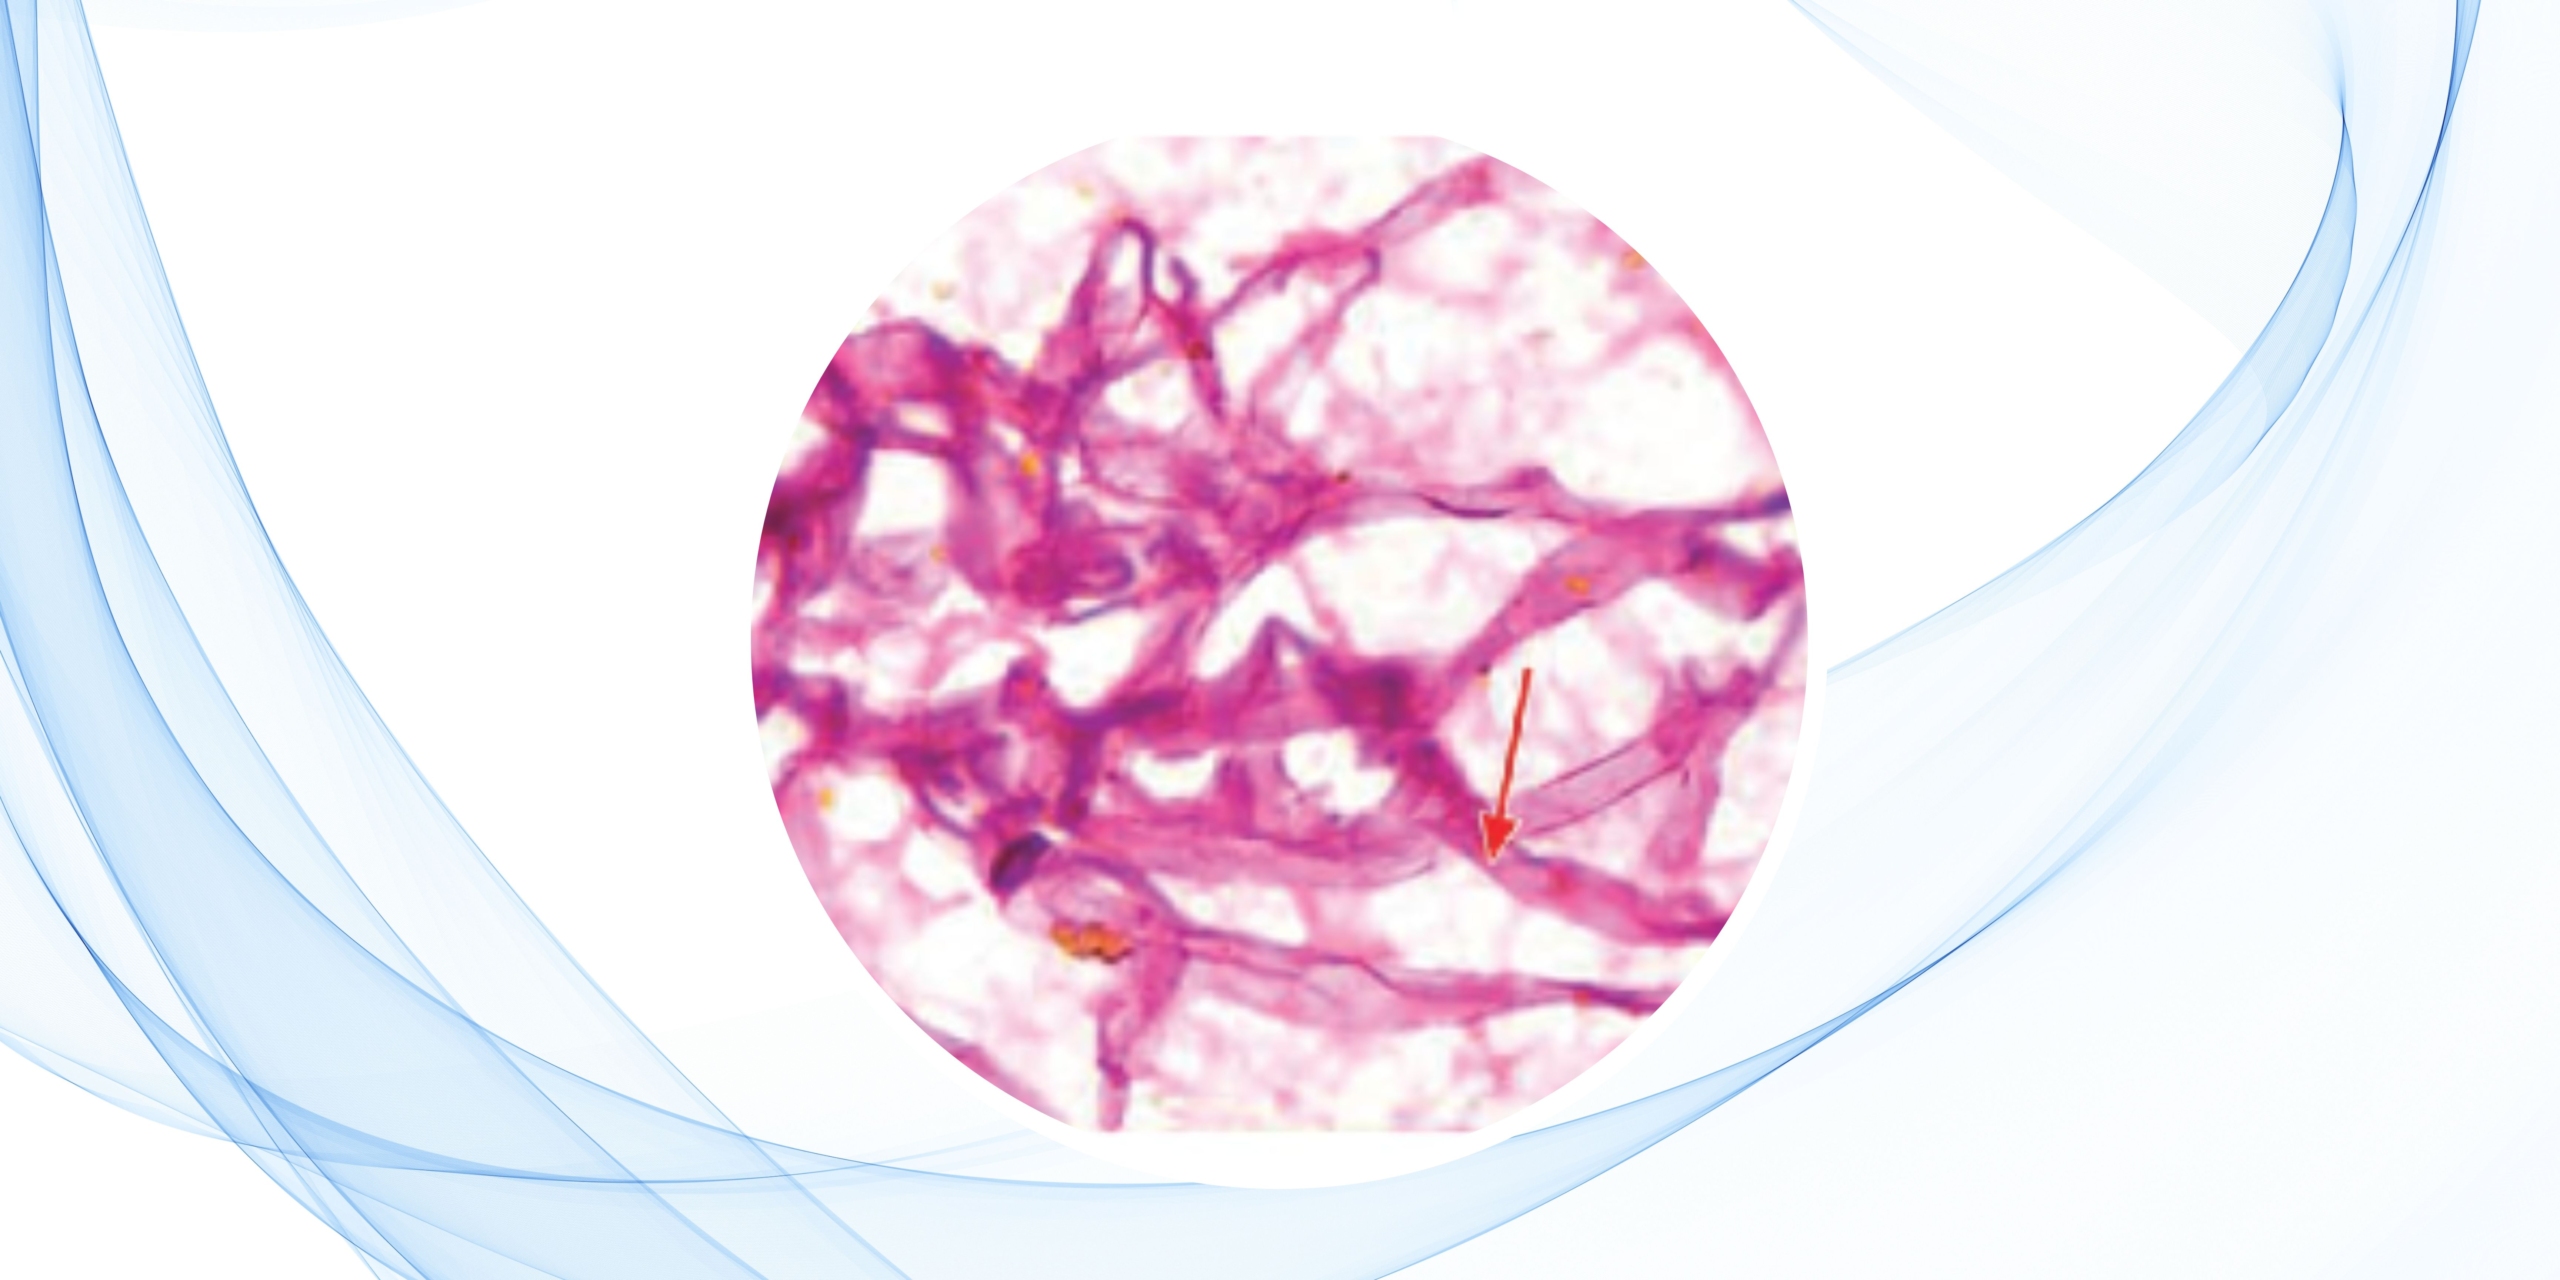

Asimismo, en casos de sospecha infecciosa, el material obtenido puede emplearse para estudios microbiológicos o micológicos, ampliando su valor diagnóstico.

La evaluación inmediata del material aspirado (ROSE) permite verificar su calidad y evitar muestras no representativas. Posteriormente, pueden aplicarse diversas técnicas auxiliares como:

- Inmunocitoquímica

- Citometría de flujo

- Estudios moleculares

Estas herramientas son fundamentales para un diagnóstico más preciso y la correcta clasificación de enfermedades, especialmente en oncología.